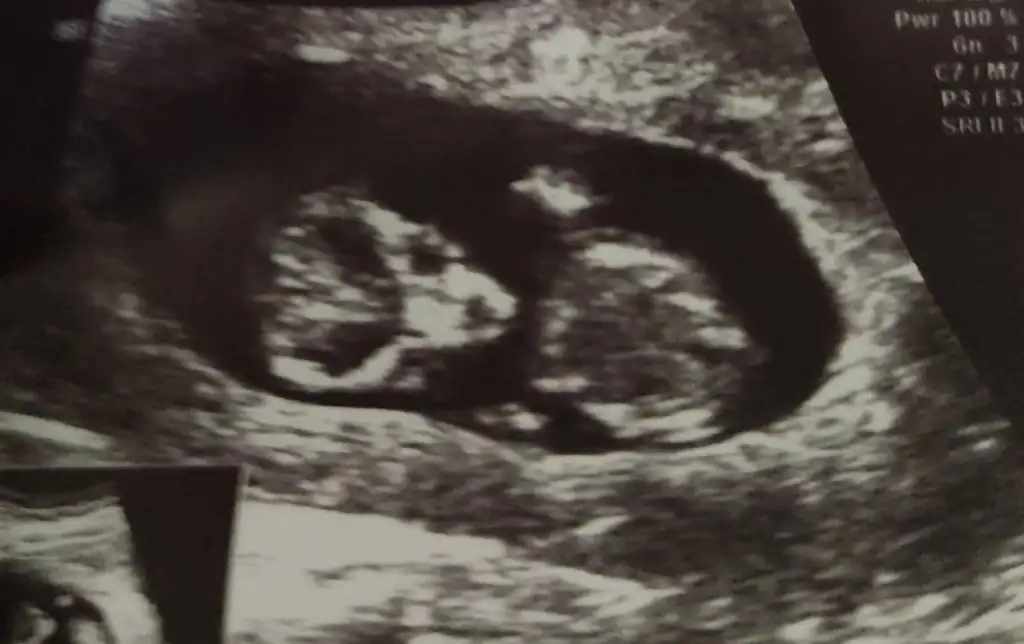

Arkadaşlar merhaba bugün doktora gittim ve bebeğimi gördüm ve sanırım biraz inatçı ense kalınlığını bile ölçtürmeye hiç yanaşmadı kıpırdandı durdu 10+3 haftadayım sizce cinsiyetle ilgili bir şey söylenebilir mi?

Hayırlısı olsun sağlıkla gelsin erkek gibi duruyor